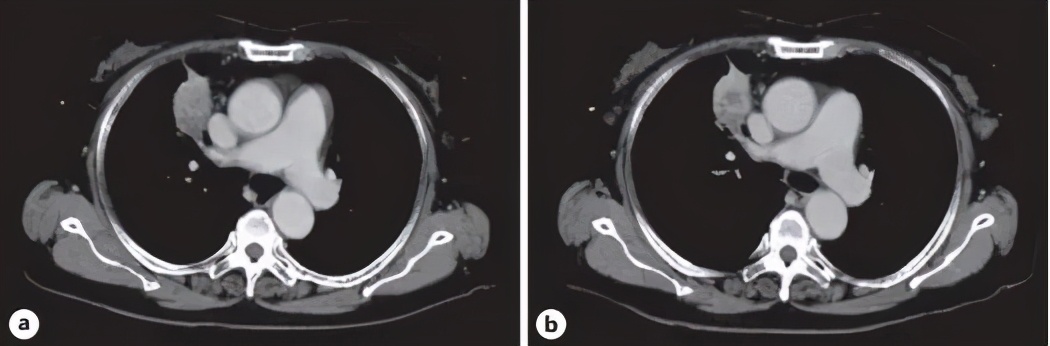

图注:给药期间胸部CT图像 。 a.2019年7月1日口服芬苯达唑之前的CT表现 。 b .2019年8月15日 , 服用芬苯达唑约1个月后CT表现 。

使用芬苯达唑后 , 患者的CEA水平略有升高(即52.7 ~ 76.7 ng/mL) , 并且2019年8月15日的CT扫描未见肿瘤大小变化 。